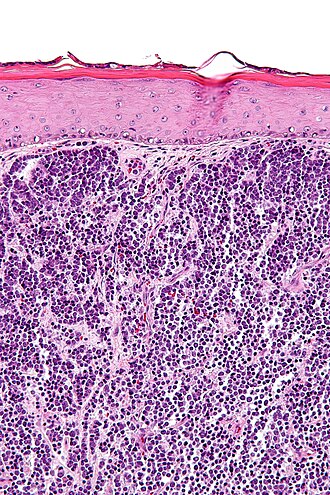

Merkel cell carcinoma. H&E stain. | |

| LM | neuroendocrine nuclear features (round nucleus, small nucleoli/no nucleolus, stippled chromatin), usually scant cytoplasm, usually small (~3x resting lymphocyte), often in sheets |

| LM DDx | small cell carcinoma, cutaneous Ewing sarcoma, Burkitt lymphoma, other small round blue cell tumours |

Features:[4]

- Neuroendocrine nuclear features - round nucleus, small nucleoli/no nucleolus, stippled chromatin - key feature.

- Typically medium size cells ~3x resting lymphocyte.

- May be small or large.

- Architecture: nests, sheets or trabeculae.

- Scant cytoplasm.

- Abundant mitoses. †

- +/-Nuclear moulding.

- Nuclei of adjacent cells conform to one another.

- +/-Tumour infiltrating lymphocytes. ‡